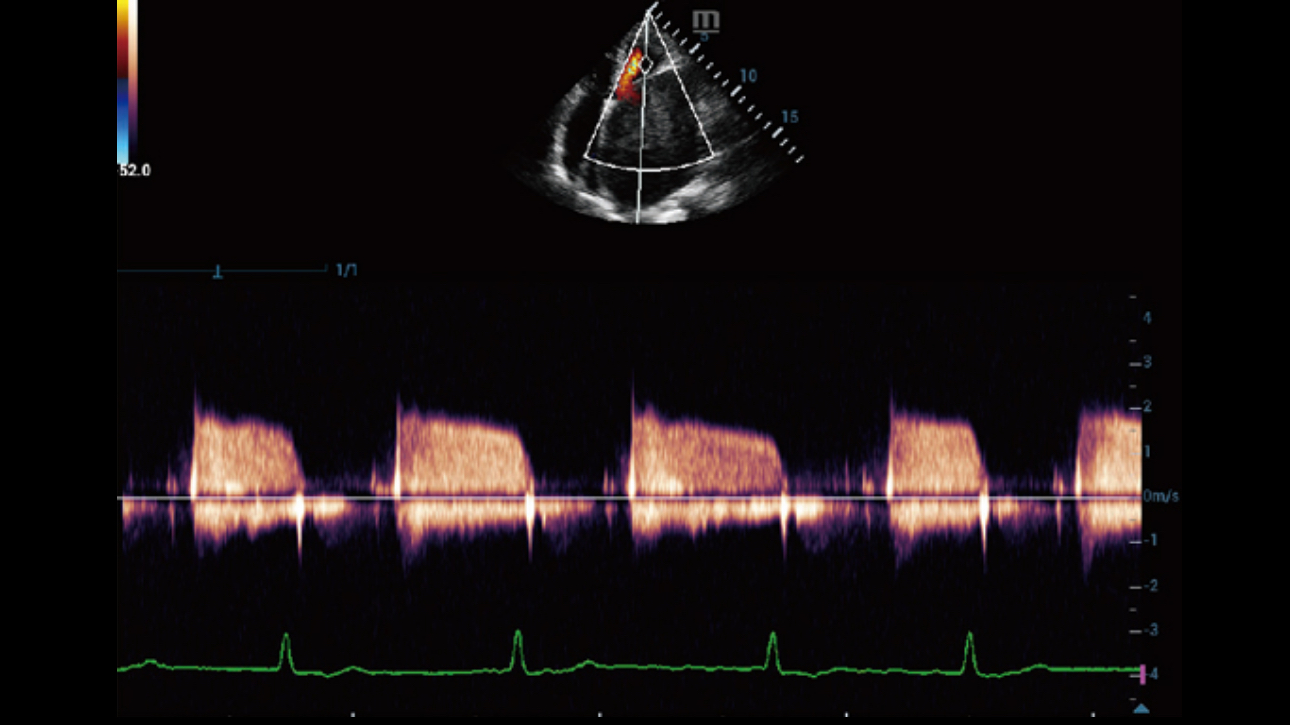

Dynamic Pixel Focusing technology allows the Resona 6 to achieve extreme uniformity in pixel level throughout the whole field of view. Now there's no need to adjust the focal positions to achieve uniformity across patient exams.

By retrospectively analyzing complete channel data stored in channel data memory, the Resona 6 is able to intelligently choose the optimal sound speed to improve image accuracy even with tissue variation, allowing for adaptive tissue-specific optimization.

Channel data based ZST+ provides Enhanced Channel Data Processing for greatly improved imaging clarity. By multiple and retrospective channel data processing, it makes the best use of acoustic information for image improvement.